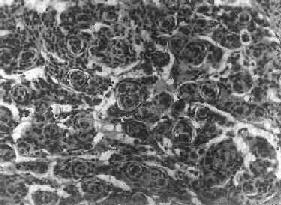

图16-27 脑膜瘤 于大脑两半球间有一近似球形肿瘤,边界清楚,周围脑组织受压萎缩 由于脑膜瘤的组织来源复杂,其组织学图像也可呈现下列基本类型: (1)脑膜细胞型(融合细胞型):瘤细胞胞浆丰富,边界不清楚,胞核椭圆形,细胞排列呈分叶状或旋涡状,为纤维间质条索所分隔。 (2)纤维细胞型:瘤细胞呈长梭形,排列成致密的交织束状结构,其间有网状纤维及胶原纤维,有时胞核呈栅状排列。 (3)过度(混合)型:脑膜细胞与纤维细胞混合,排列成分叶状,中央为脑膜细胞,周围为纤维细胞,常形成旋涡状结构(图16-28),其中常包含有同心层状结构的砂粒体,乃变性肿瘤细胞及钙盐沉积。肿瘤质地硬,似砂砾状。

图16-28 脑膜瘤 瘤细胞为圆形或多角形,作旋涡状排列 (4)血管母细胞型:肿瘤细胞丰富,胞浆模糊,胞核椭圆,多排列在毛细血管旁,并有较多的网状纤维。 各型脑膜瘤中均可有不同程度的出血、钙化,有些并有黄色瘤细胞、软骨、骨、黑色素及粘液样变。 大多数脑膜瘤为良性,瘤细胞可引起邻近颅骨的骨质增生,或肿瘤浸润,但不引起广泛播散或转移,也不侵入邻近的神经组织。一般手术后复发率可达15%,其中血管母细胞型有复发和播散倾向,预后较差。少数脑膜瘤细胞间变明显,与梭形细胞肉瘤难以区分,可发生颅外转移,主要累及肺及淋巴结。